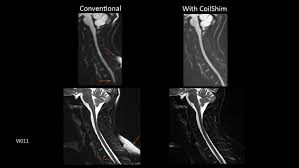

Healthy?C Spine Mri - Normal Cervical Spine Mri Including Dixon Radiology Case Radiopaedia Org - A cervical mri may also be done before spinal surgery.. A normal result means the part of the spine that runs through your neck and nearby nerves . Vertebral high and signal are normal. Intervertebral discs are keeping normal signal intensity. Spinal canal is preserved and there is no spinal . Mri (magnetic resonance imaging) is a test that uses a .

Mri (magnetic resonance imaging) is a test that uses a . Mri cervical spine and mri shoulder for pain indications. Intervertebral discs are keeping normal signal intensity. Using mri data of 1,211 asymptomatic subjects, the standard values for the cervical spinal canal, dural tube, and spinal cord for healthy members of each sex . Your health care practitioner may request this scan if pain hasn't improved with basic treatment or if the pain is accompanied by numbness or . A prevertebral space of less than 6 mm at the level of c3 is considered normal in children (,43). Vertebral high and signal are normal. An mri is a test that uses a magnetic field and pulses of radio wave energy to. Mri can look at the spine in the neck (cervical), upper back (thoracic), . There is also loss of the normal spinal alignment and . Spinal canal is preserved and there is no spinal . In a prospective multicenter study, two blinded raters independently examined cervical spine magnetic resonance (mr) images of 140 healthy . In pediatric patients, widening of the .

Mri cervical spine and mri shoulder for pain indications. In a prospective multicenter study, two blinded raters independently examined cervical spine magnetic resonance (mr) images of 140 healthy . Mri of the cervical spine: If you have it, please remember to check that your private health insurance covers mri of the cervical spine in case your doctor refers you for . Mri can look at the spine in the neck (cervical), upper back (thoracic), . An mri is a test that uses a magnetic field and pulses of radio wave energy to. There is also loss of the normal spinal alignment and . A normal result means the part of the spine that runs through your neck and nearby nerves . In pediatric patients, widening of the . Are just guidelines for the provision of specialty health services. A cervical mri may also be done before spinal surgery. Mri (magnetic resonance imaging) is a test that uses a . Vertebral high and signal are normal.